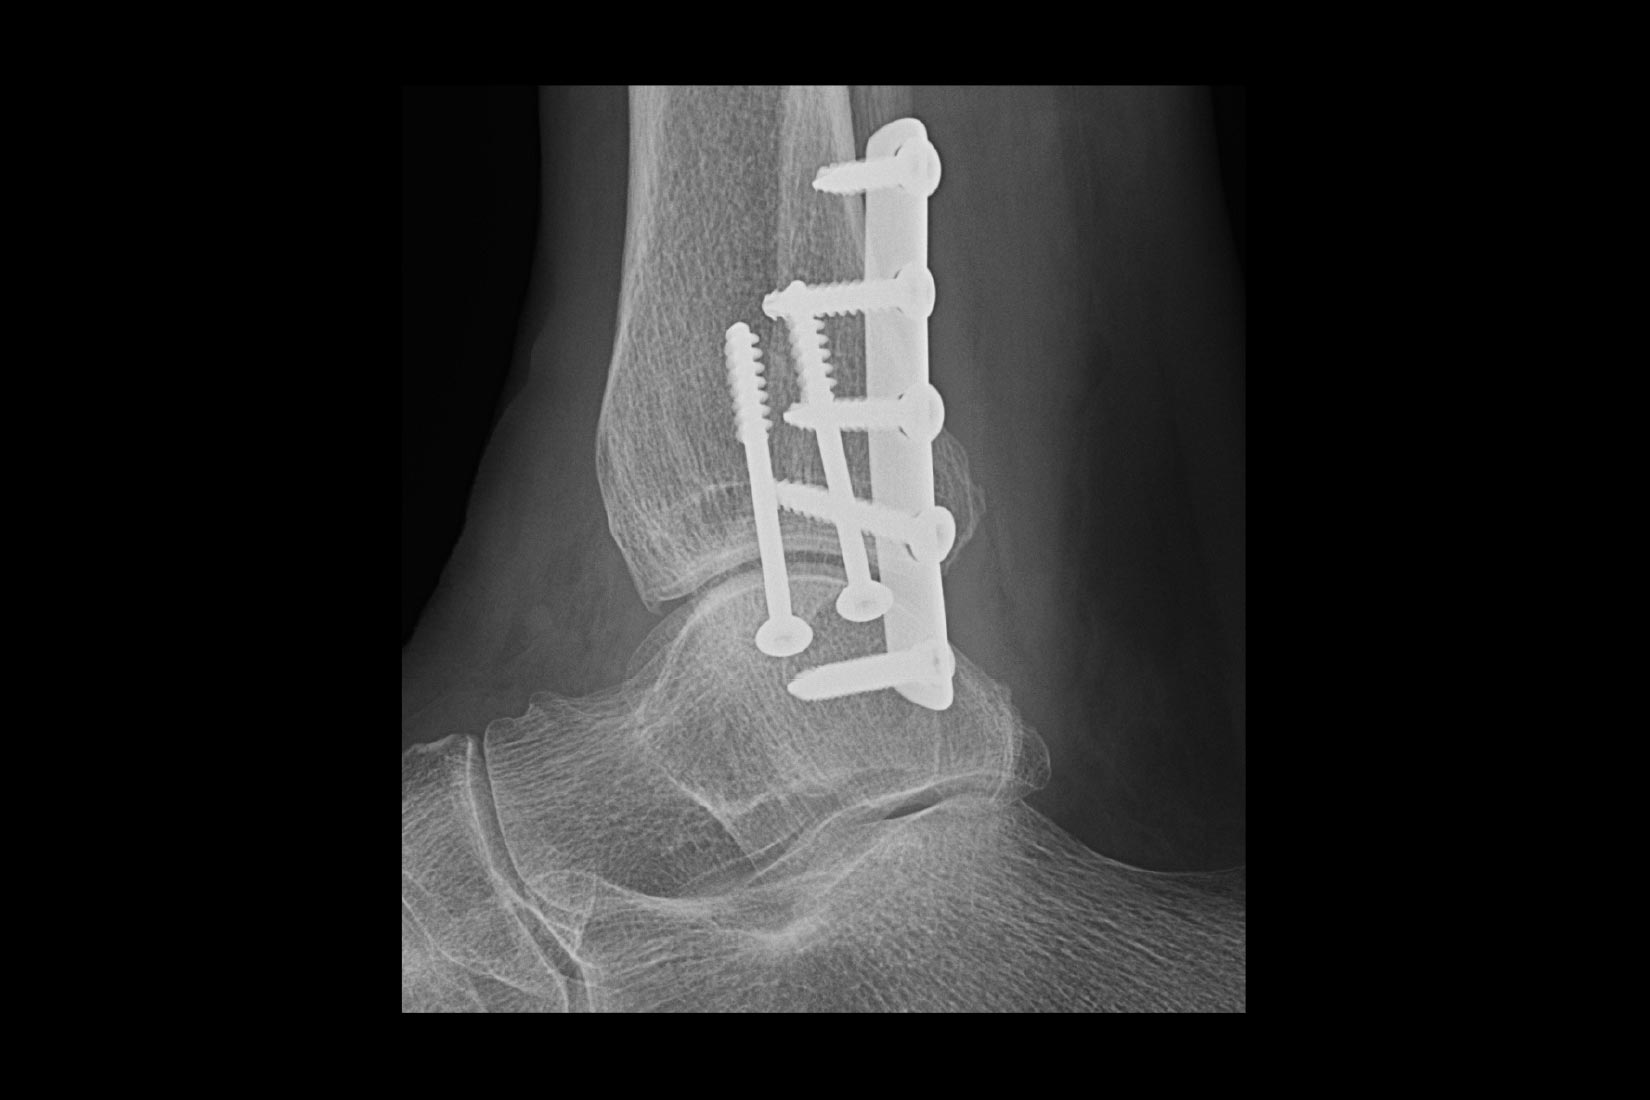

Transdutores Venue

Vivencie imagens claras em uma gama de pacientes, de adultos a pediátricos com os transdutores mais recentes para a família Venue.